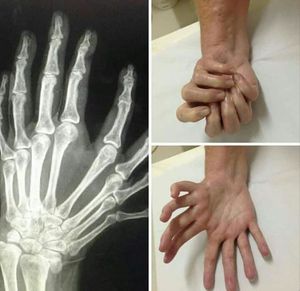

Have uh ever heard abtt " Mirror Hand Syndrome"?? Ulnar dimelia or Mirror Hand Syndrome is a rare conjenital anomaly of the upper limb characterized by absence of radius,duplication of ulna and symmetric polydactyly(7or8 fingers and lack of thumb. Less than 100 cases have been reported in the literature till today!!!